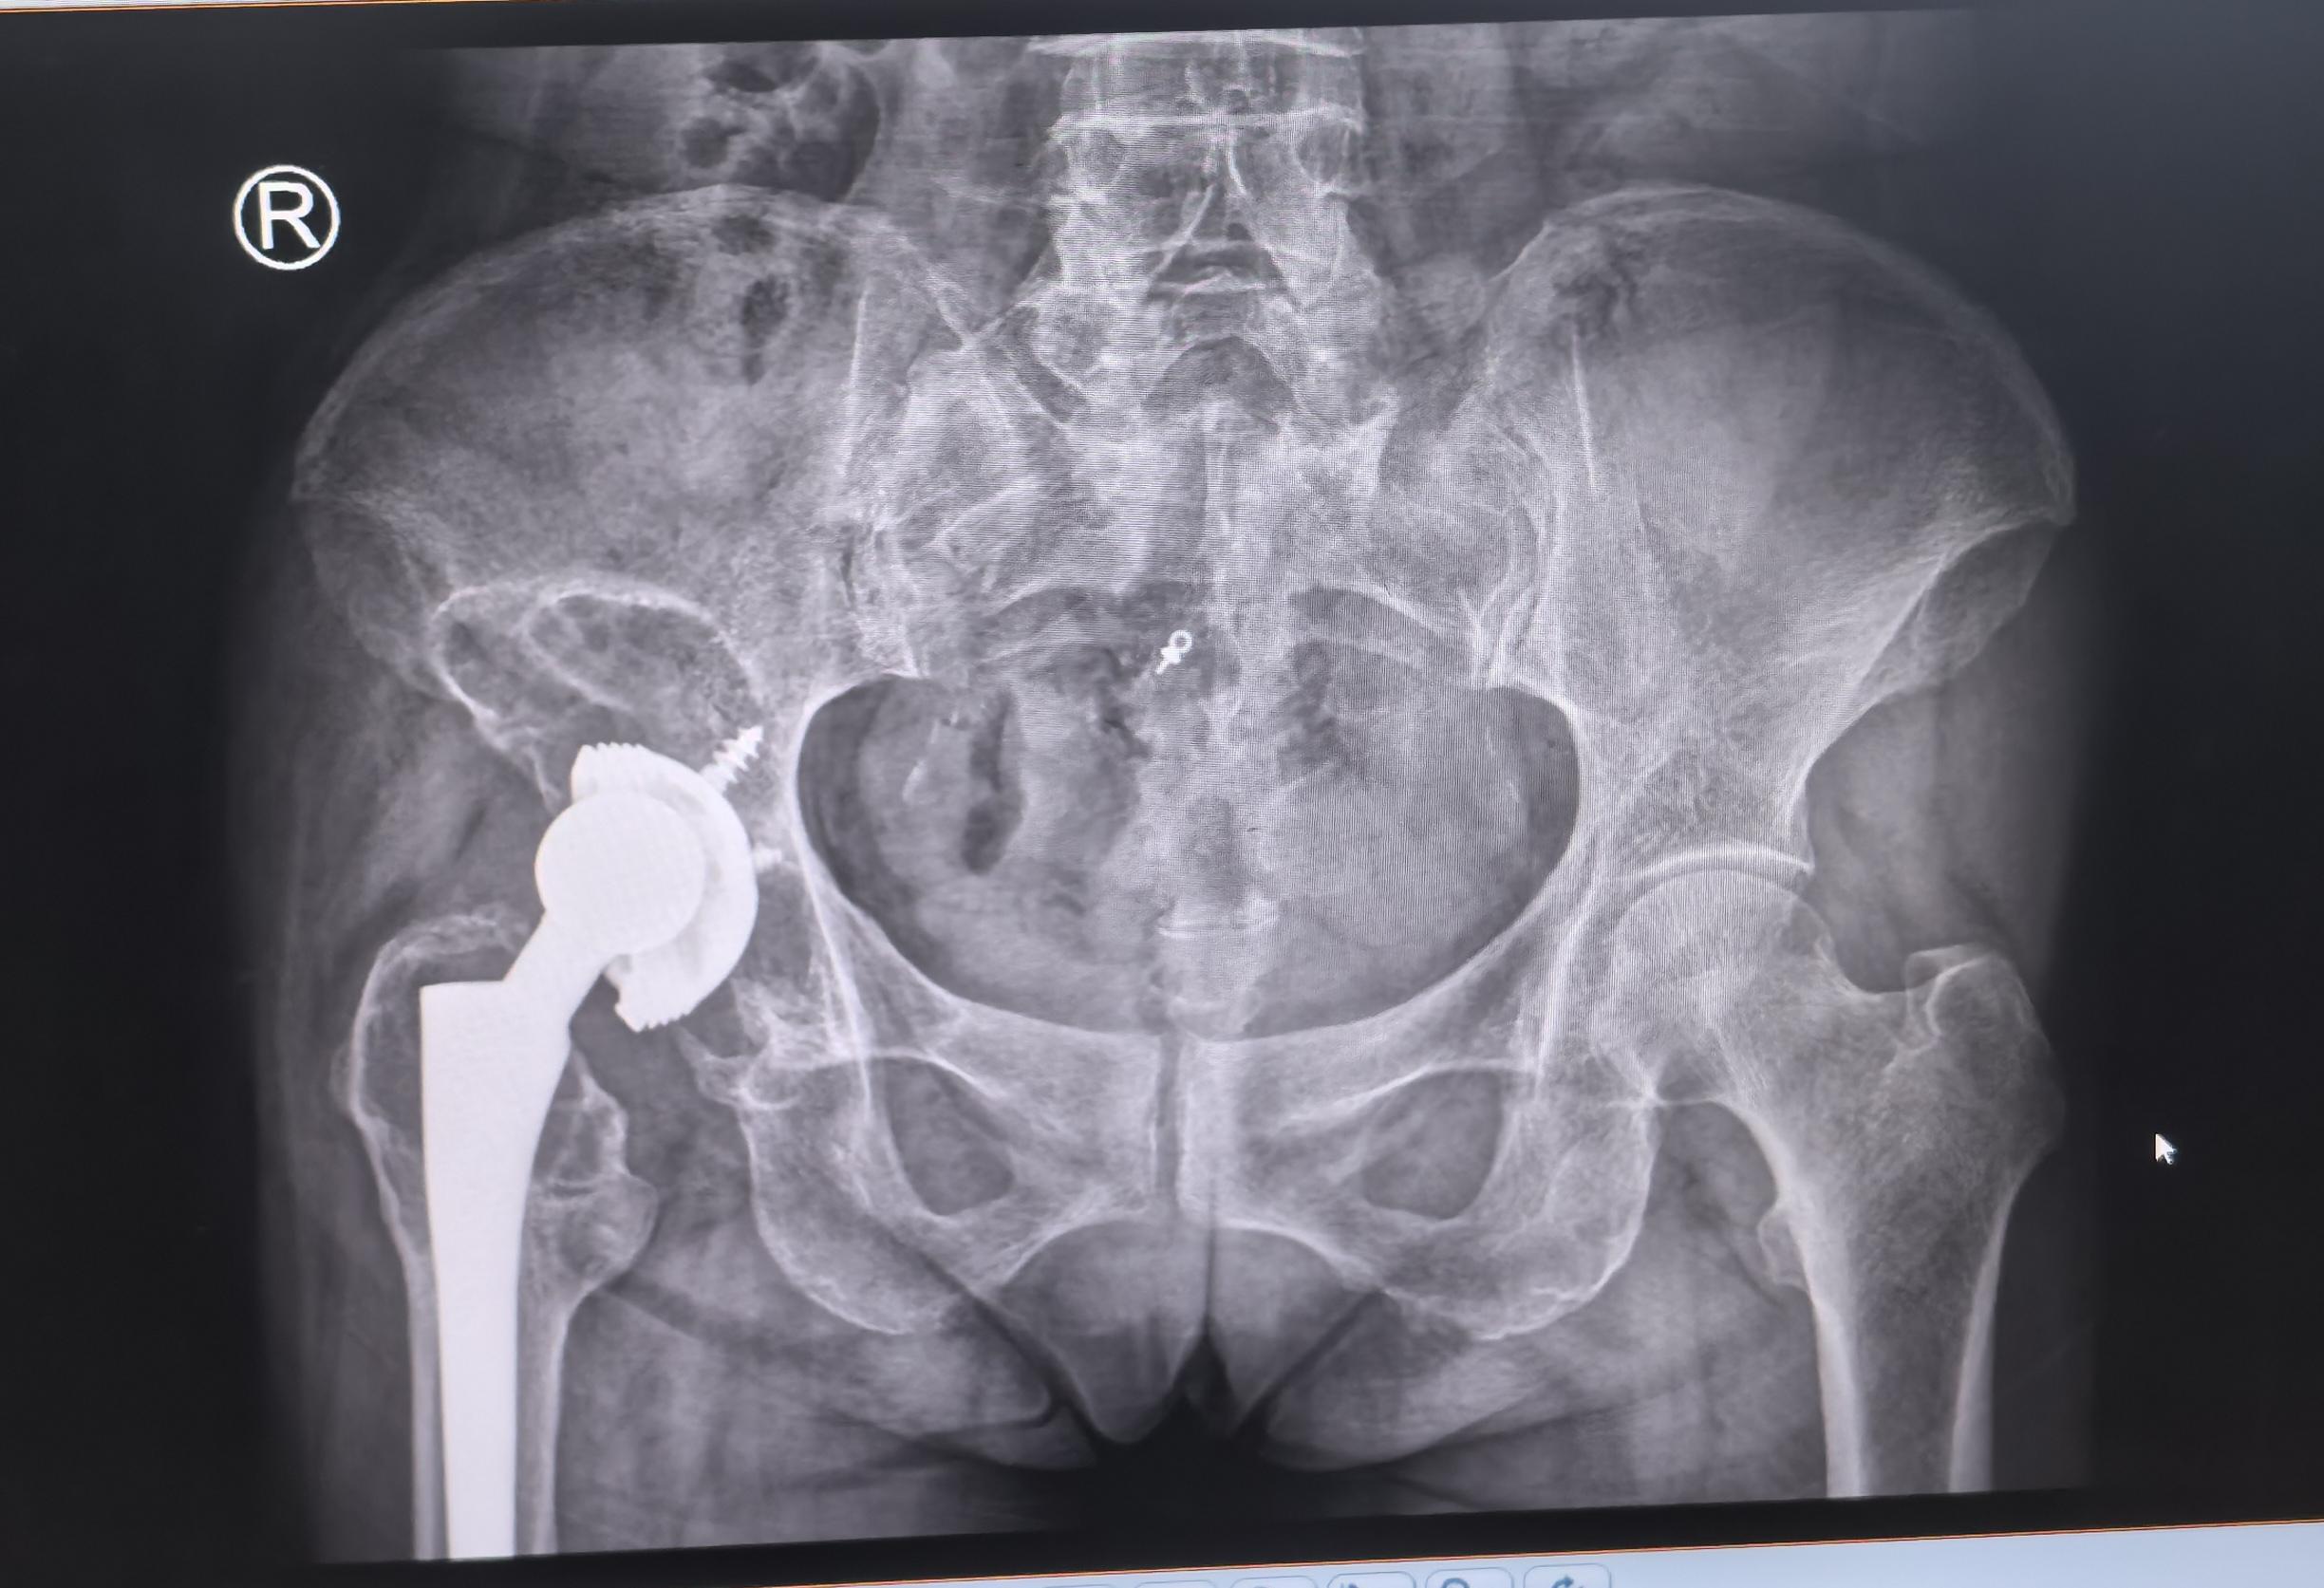

全髋关节翻修术。82岁老太太,THA后(14年)假体松动、骨溶解,全髋翻修,再续20年🌹